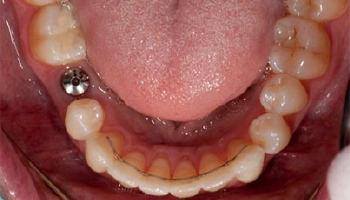

Implant retained lower denture

Before and after photos of an implant retained lower denture. Comparison of lower denture before and after implant retention.